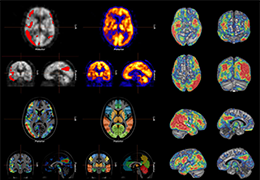

ANYTHINK 经导管主动脉瓣膜置换术分析系统